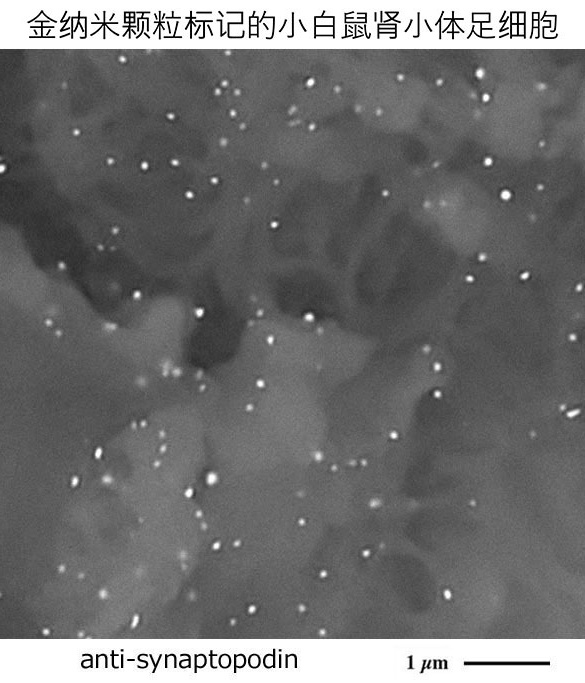

开发出一种可视化生物物质定位的全新金纳米颗粒标记法

Development of a new gold nanoparticle labeling method for visualizing the localization of biological materials by utilizing the advantages and properties of desktop low-vacuum scanning electron microscopy

我们开发了一种新型金纳米颗粒标记法,该方法基于酶标抗体法免疫组化染色的石蜡切片,通过氯化金处理原位生长金纳米颗粒,从而轻松实现目标生物物质的定位可视化。

We have developed a new gold nanoparticle labeling method that allows easy visualization of the localization of target biological material by growing gold nanoparticles formed by treating with gold chloride on paraffin sections stained with immunohistochemistry using an enzyme-antibody method.